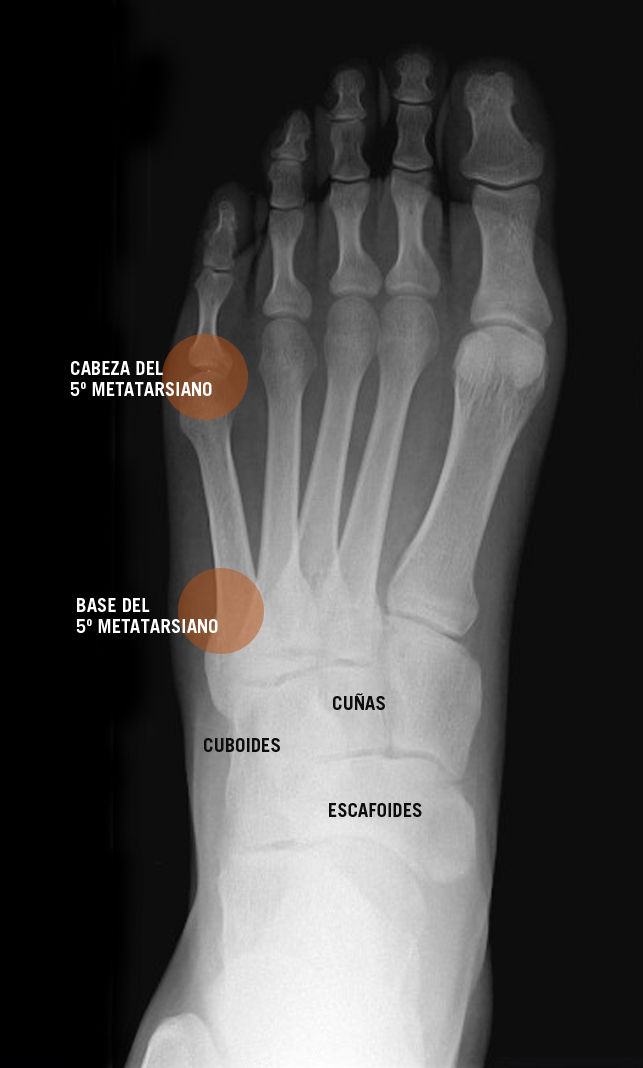

From clinicayecla.es

FRACTURAS DEL QUINTO METATARSIANO Clinica Yecla Quinto Metatarsiano Fractura Las fracturas de la base suelen denominarse como fractura de seudo jones o de la bailarina. This activity describes the evaluation and. El quinto metatarsiano es el hueso que sufre fractura con mayor frecuencia. Su estructura anatómica se divide en: Fracturas de la base del quinto metatarsiano. La zona proximal del 5to mt se divide en 3 zonas (zona 1,. Quinto Metatarsiano Fractura.